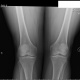

Рис. 58, а, б. Обызвествление полулунных хрящей менисков в обоих коленных суставах.

Больной К., 60 лет, жалуется на перемежающие боли в обоих коленных суставах, хруст при движениях. Боли незначительные. Видимых изменений в коленных суставах нет. Подвижность достаточная. В отроческие годы часто страдал заболеванием коленных суставов, которое трактовалось тогда как ревматизм. В дальнейшем заболевания суставов прошли и больной о них забыл, лишь иногда чувствовались незначительные боли в коленных суставах. В последние годы боли стали ощущаться все чаще.

Рентгенологическое исследование: в костях суставов изменений не обнаружено; суставные щели нормальной ширины; определяются обызвествления менисков в обоих коленных суставах.